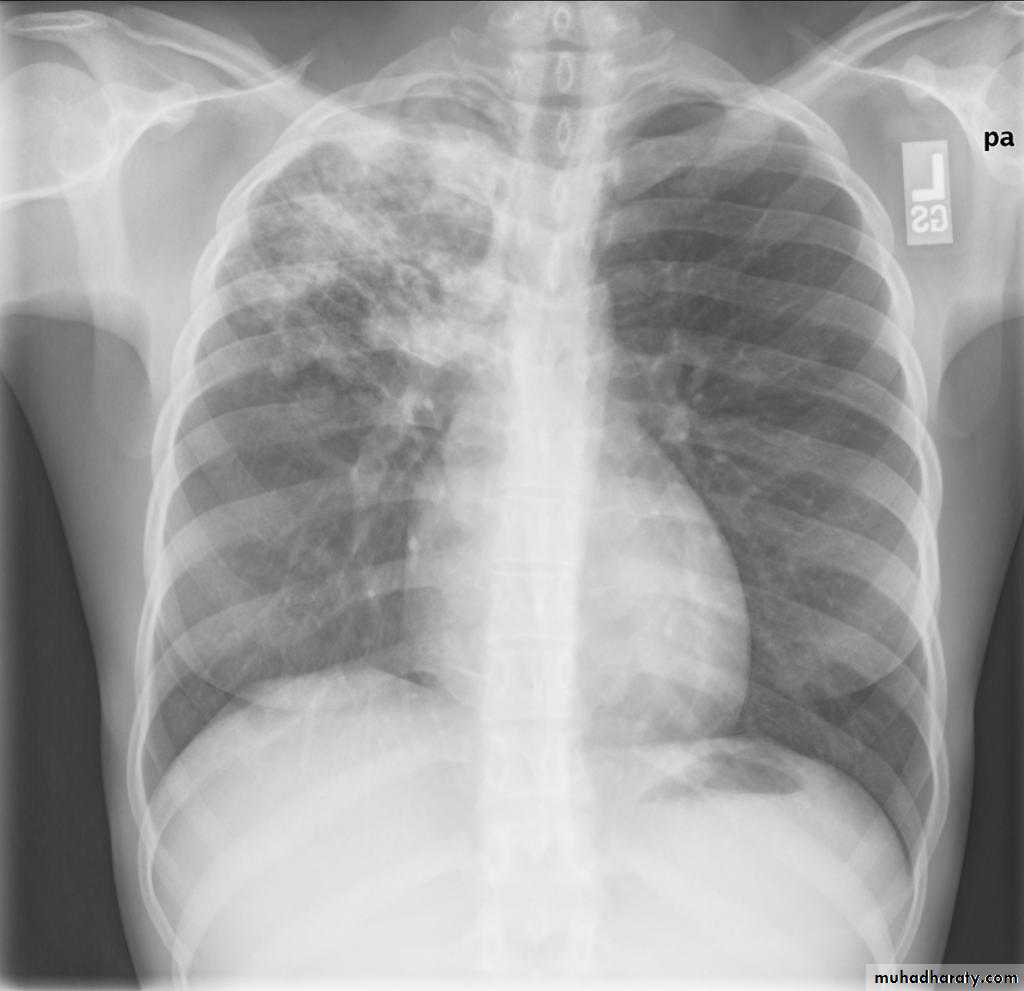

Post primary TB radiographic appearance

Post-primary pulmonary tuberculosis, also known as reactivation tuberculosis or secondary tuberculosis occurs years later, frequently in the setting of a decreased immune status. In the majority of cases, post-primary TB within the lungs develops in either :

* posterior segments of the upper lobes

*superior segments of the lower lobes

Typical appearance of post-primary TB

1.patchy consolidation or poorly defined linear and nodular opacities in both apices , upper zone in one lung , & lower zone in other lung ( ulternating lesion ) .2. Post-primary infections are far more likely to cavitate with multiple abscess formation & air fluid level more develop in the posterior segments of the upper lobes.

3. Tuberculomas seen in post-primary TB and appear as a well defined rounded mass typically located in the upper lobes .